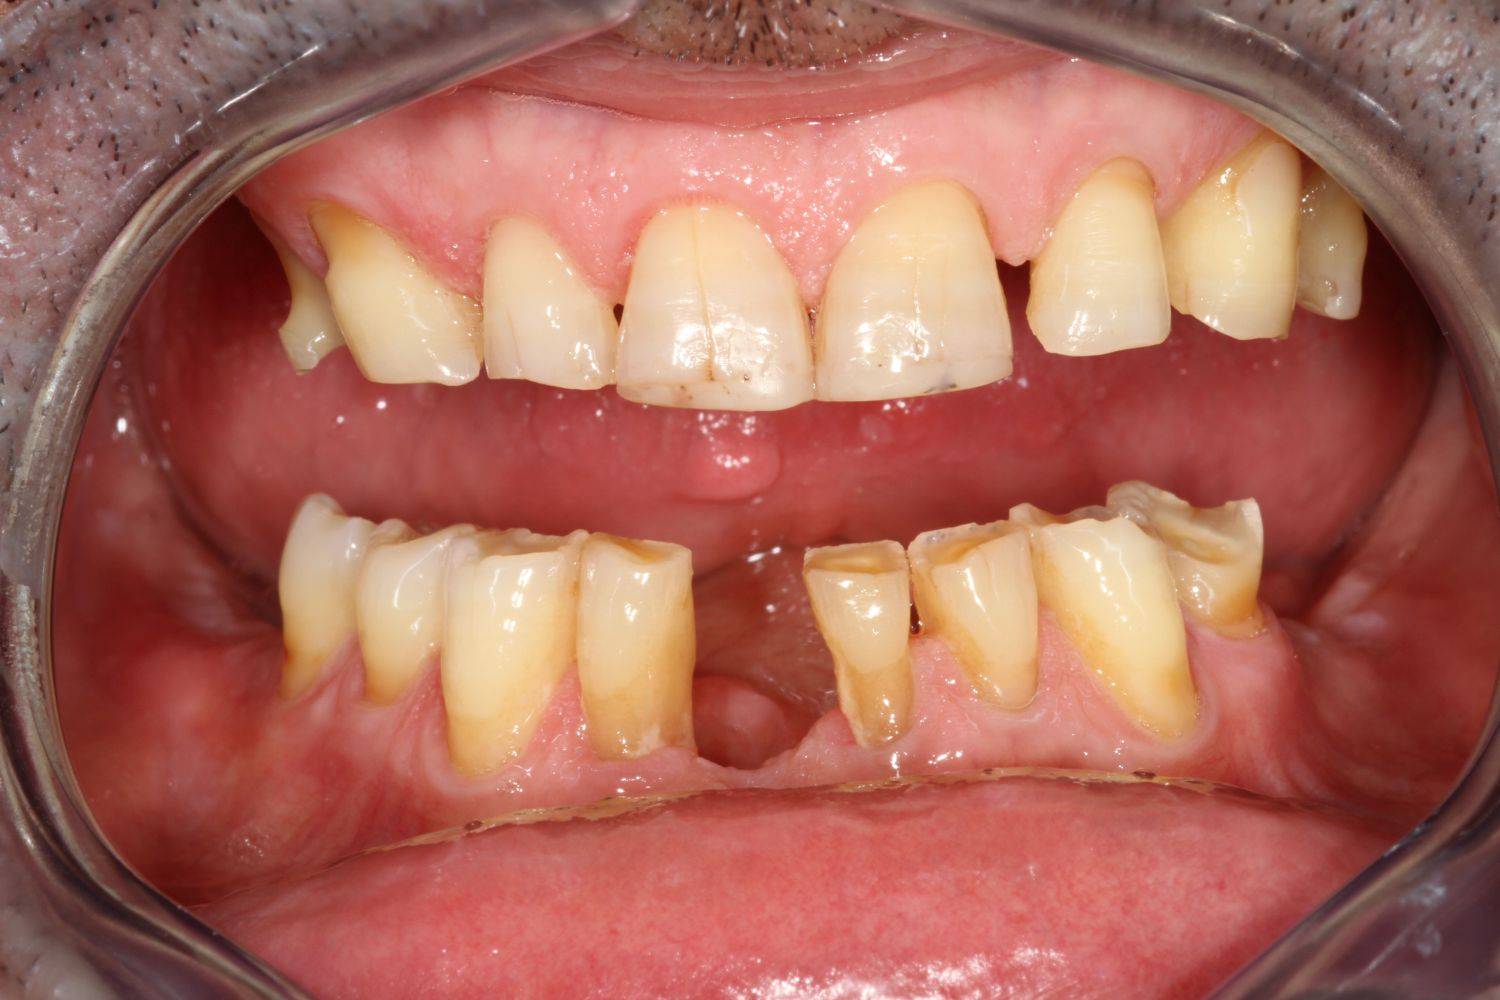

6. Eset

Nagymértékű fogkopás, erózió, csikorgatás a teljes rágóapparátust túlterhelve okoz reménytelennek tűnő helyzeteket.

Ebben az esetben implantátumok , koronák és hidak segítségével változtattunk a páciens fogainak érintkezésén. 6 hónapig ideiglenes hidakkal teszteltük a megváltoztatott harapási pozíciót. Ezután készültek el a végleges fix pótlások.